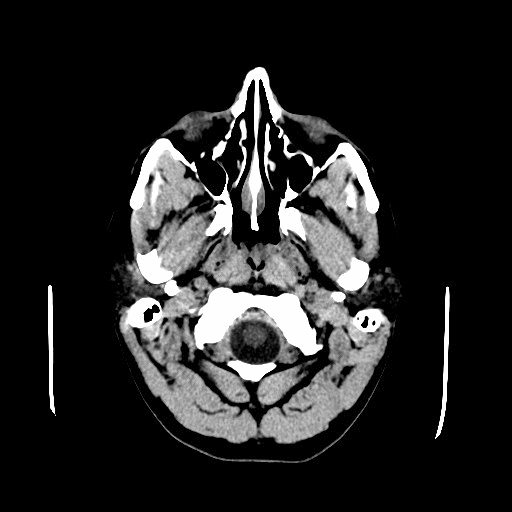

CT-scan van een colloïdcyste (rood omcirkeld) die links in het brein zit nabij het foramen van Monroe. Je ziet dat de voorhoorn van het linkerzijventrikel ook aanzienlijk wijder is dan de voorhoorn van het rechterzijventrikel. Dit komt door een afvloedobstructie van liquor. Credits voor afbeelding: ‘TImeholder’, CC BY 3.0.

- Obstructie van de afvloed van liquor (bijv. een cerebellaire tumor die het gehele vierde ventrikel dichtduwt)